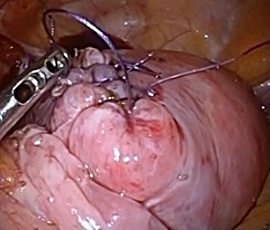

腹腔鏡下胃切除術の実際

全身麻酔下で手術を行います。まず腹腔内(腹腔:お腹の壁と臓器との間の空間)に炭酸

ガスを入れて膨らませ、お臍からカメラ(腹腔鏡)を挿入します。同時に手術操作に用い

る器具(鉗子など)を挿入するための5〜10mmの小さな穴を左右に4カ所開けます。そ

して腹腔鏡で撮ったお腹の中の様子をモニターに映し出して、胃切除や周囲のリンパ節

の切除を行います。開腹手術では見えにくかった細い血管や神経まで見えて繊細な手術

操作が可能です。

胃切除、切除後の再建を体外で行う場合は、開腹手術ほど大きな創にはなりませんが、

どうしても5〜7cmの切開創(傷)が必要となります。(腹腔鏡補助下胃切除術)

現在当院では、胃切除・切除後の再建を体内で行うため、切除した胃を取り出すための

切開創(傷)はお臍の上約2〜3cmで十分であり、腹腔鏡補助下での手術よりも更に小さ

な創で手術を完遂する事が可能となります。(完全腹腔鏡下胃切除術)

当院での腹腔鏡下胃切除術は「完全腹腔鏡下胃切除術」を主に行っています。

完全腹腔鏡下幽門側胃切除術

(胃の出口(幽門)を含めて胃の下方約2/3を切除する術式)

胃の全体 十二指腸離断

左胃動脈 胃切離

残胃−十二指腸吻合 吻合終了

完全腹腔鏡下胃全摘術 (胃の全てを切除する術式)

食道離断 挙上空腸作製

食道−空腸吻合 吻合終了